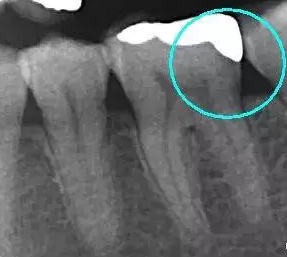

從下面這張X線中可以看出,嵌體遠中邊緣沒有懸突,與牙體邊緣密合相接。